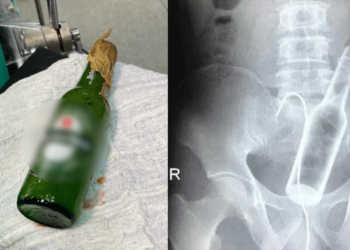

BRASIL - Durante uma noite de cachaçada, um jovem de 25 anos, pasosu por um sufoco, após enfiar uma garrafa ...